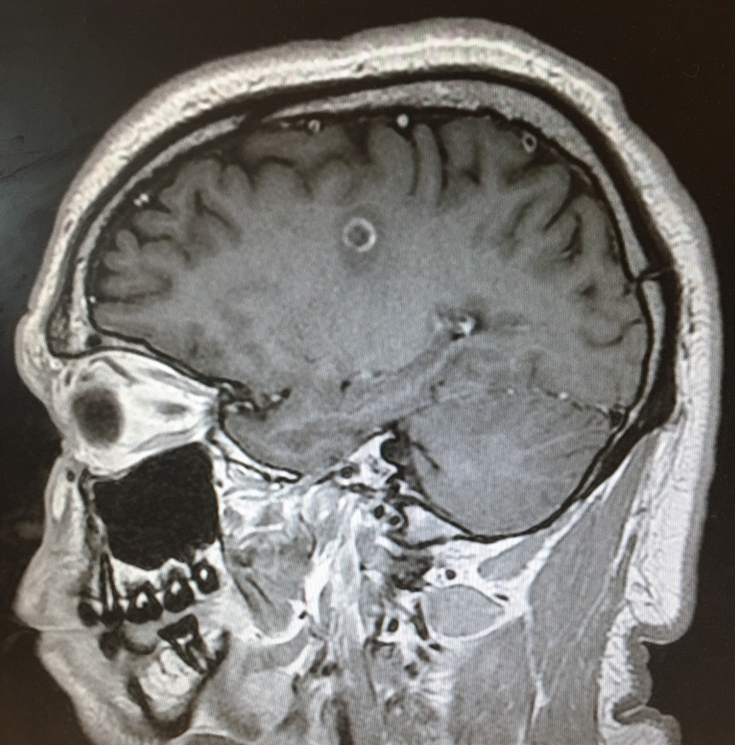

Magnetic resonance imaging (MRI) scans of the brain showed an abnormal area of increased signal intensity in the left centrum semiovale measuring approximately 1.8 cm, and another in the left periatrial region measuring approximately 1.2 cm (Figure 1). The lesion at the semiovale showed ring enhancement on one view, which prompted a differential diagnosis of neurocysticercosis (Figure 2).

Figure 2. The lesion in the left corona radiata/centrum semiovale showed ring enhancement.